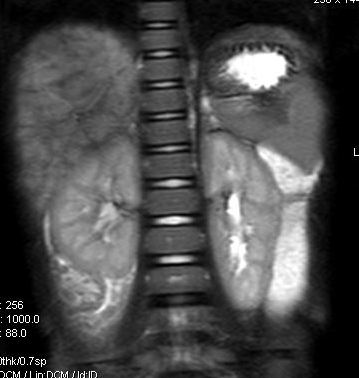

标题: V0176(MRI):小儿发热,肝脾大,肝内病变 [打印本页]

标题: V0176(MRI):小儿发热,肝脾大,肝内病变

5岁,2006年8月曾行阑尾炎手术,现发热半年